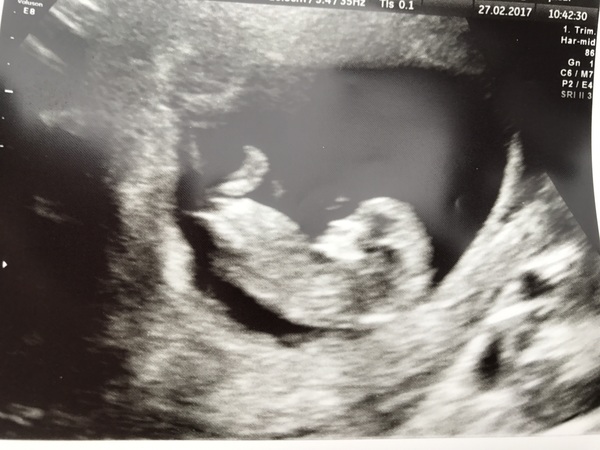

Kskifred · 27/02/2017 22:04

also based on nub theory what are you guys thinking? bit of fun!

if where i think is the nub is right on yours ks im saying girl Smile

Thanks Ginger! I was thinking girl too Smile

Kskifred · 28/02/2017 20:37

Ooh this is fun!

newbie and argon I would guess both boys although I'm no pro! Been reading up on in-gender.com which is quite interesting, the genitals look identical at the stage!

actually the more i look at newbie it could be girl, that's not much help is it! argon i'm still sticking with boy Grin